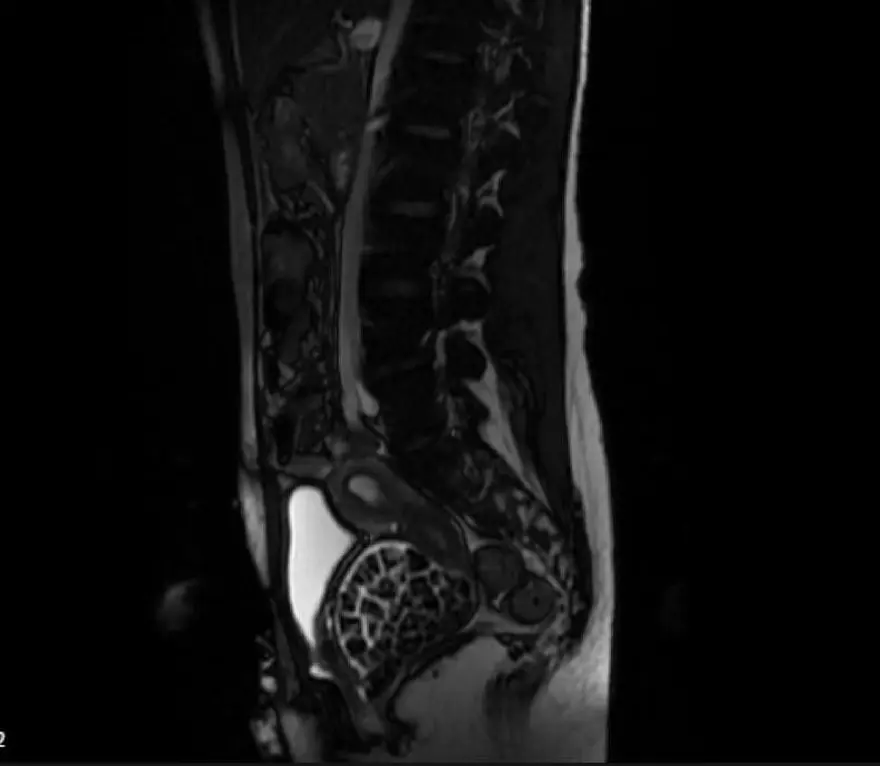

Burada ekipleri tarafından hastanın durumuna ilişkin detaylı incelemeler yapıldı. 2 bölümün iş birliğinde titizlikle yapılan tetkiklerde uzmanlar, vajen isimli noktada taşlar olduğunu tespit etti, Öztürk'ün hemen yatışı yapıldı.

Öztürk’ün vücudundan 287 adet çeşitli ölçülerde taş çıkarılırken üroloji ve jinekolojik onkoloji ekibi operasyonu başarıyla tamamladı. Taşların sayısını duyan genç kız ve ailesi şok olurken operasyonun ardından karın ağrıları dinen Öztürk, rahat bir nefes aldı. Tedavisi sonrası taburcu edilen genç kız yaşadıklarını anlatırken, operasyonu gerçekleştiren doktorlar, genç kızın vücudundaki 287 taşın tetkiklerdeki görüntüsü dikkat çekerken taşlar üzerine de incelemeler yapılacak.

Bir başka uzman da, "Konjental anomali, bunu gebelik esnasında yapmış olduğumuz ultrasongrafi muayenelerinde saptayabiliyoruz. Maksimum 100-110 kadar bir taş vardır diye bir düşüncemiz vardı, sayalım dedik. 287 taş da bizi ameliyat esnasında heyecanlandırmıştı. Saydıktan sonra bu bilgiyi hastamız ve ailesiyle paylaştık. Onlar da şaşkınlık halindeydi, böbrek taşını düşüren bir kişiyle konuştuğunuz zaman bir taşın bile ne kadar zor bir şekilde düştüğünü size tarif edecektir. Taşların uzun yıllar boyunca yavaş yavaş oluştuğunu düşünüyoruz." bilgisini aktardı.